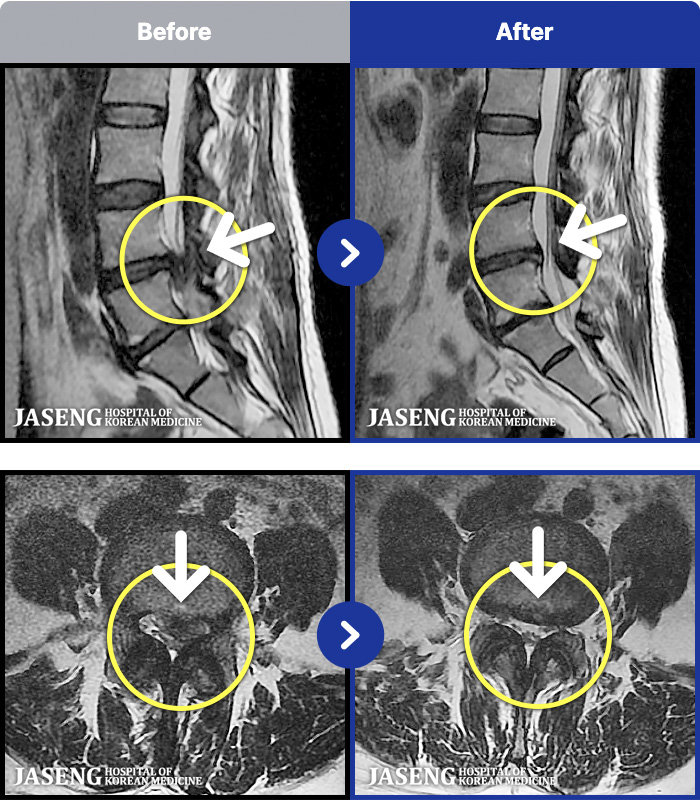

1,291 MRI ũ ʸ Ȯϼ.

[뱸] 19.11.28~25.05.06